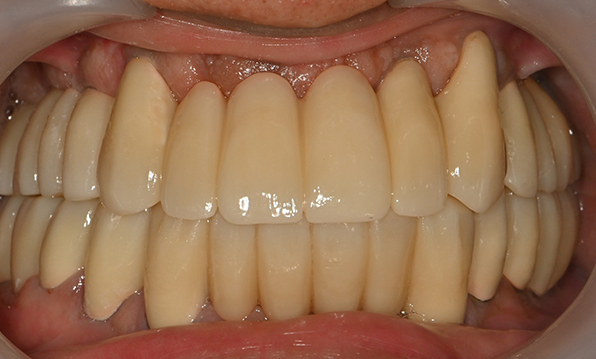

전체 임플란트

위 아래 치아가 정확하게 맞아야하는 고난이도 임플란트

치아가 하나도 남아있지 않거나 전체적으로 상실된 경우 추천합니다.

치료기간 : 2021.04.12~2021.09.15